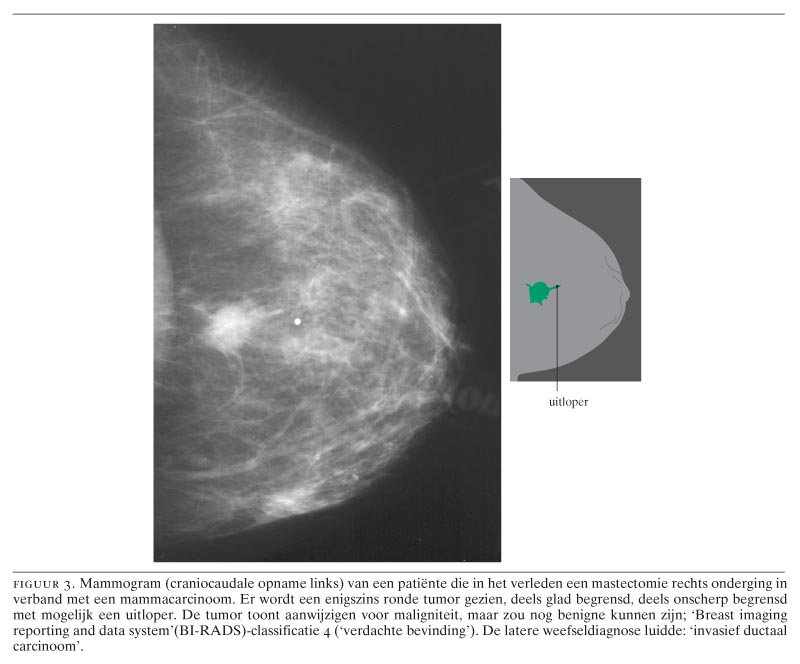

De voorspellende waarde van classificatie van mammografie-uitslagen volgens het 'Breast imaging reporting and data system' (BI-RADS): retrospectief follow-uponderzoek in een ziekenhuispopulatie | NTvG